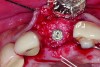

In cases with an incomplete facial plate, the ice cone technique was recommended.20 In this method, a collagen membrane was trimmed to the shape of an ice cone and placed into the socket against the inner aspect of the facial bone. The socket was filled with bone substitutes, and the coronal portion of the membrane was used to cover and protect the underlying bone substitutes. A non-resorbable PTFE membrane can be used for site preservation as well.21 This membrane, if secured to bone, can be left exposed, and epithelialization will occur over it. It was found that sockets grafted with a mineralized bone allograft and PTFE membrane had 47.4% new bone formation and 14.7% residual graft particles. In addition, there was minimum resorption of the buccal bone thickness, as indicated by a 0.3-mm horizontal bone resorption and a 0.25-mm vertical bone resorption.22 A recent systematic review reported that the use of PTFE membranes in ridge preservation shows potential in maintaining ridge dimensions23 and possibly aiding in increasing the zone of keratinized mucosa. Therefore, the use of PTFE membrane may be preferred in ridge preservation of sites in the esthetic zone. Figure 1 and Figure 2 illustrate the use of PTFE membrane in ridge preservation for implant replacement in the esthetic zone. Other authors have also attempted primary closure of the socket or to improve the ridge topography with soft-tissue grafts, but it has not been proven to be effective in increasing bone regeneration.18

Placement of implant. Notice the bucco-palatal bone thickness gained from the ridge preservation technique.